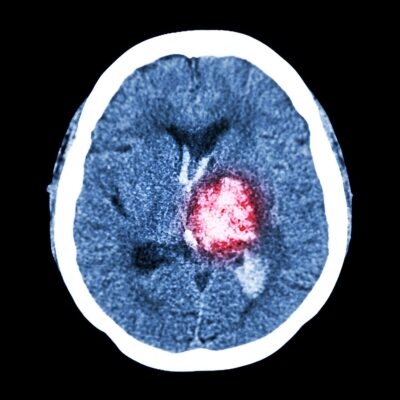

Neurosurgery is a specialized medical field focused on the diagnosis and surgical treatment of disorders affecting the brain, spine, and peripheral nerves. At Vijetha Hospital, we manage a wide spectrum of neurological conditions, from life-threatening brain injuries to minimally invasive spine procedures and peripheral nerve surgeries. Our goal is to restore function, relieve pain, and improve quality of life for our patients through precise and compassionate care.

Surgical removal and post-operative care for brain tumors. - Cerebrovascular Diseases (Aneurysms, AVMs, Stroke)

Timely surgical interventions for vascular abnormalities in the brain improve survival and recovery. - Head Injuries/Trauma

Removal of herniated disc material and bone to relieve nerve compression. - Craniotomy

Open surgical access to the brain for tumor removal, trauma, or vascular repairs. - VP Shunt placement